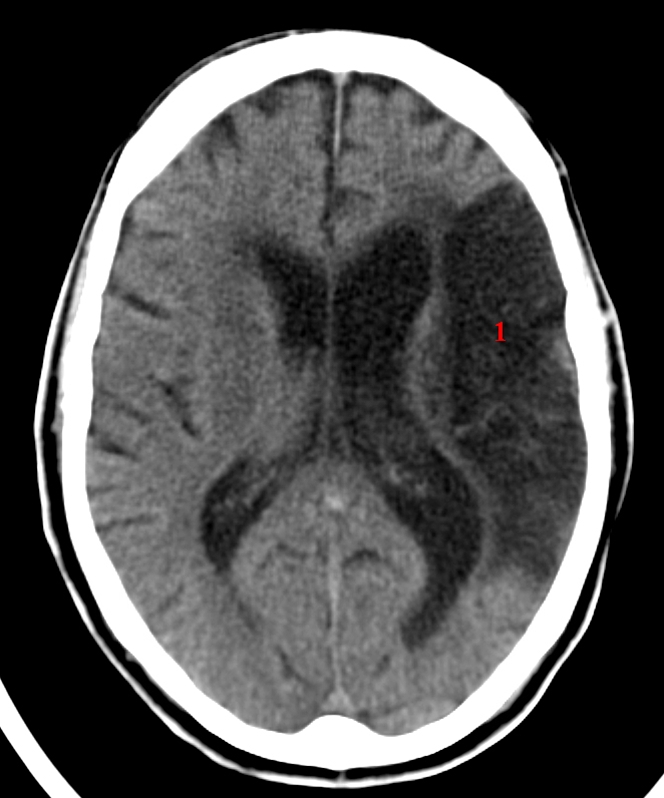

Cerebralt infarkt media (CT)

CT cerebrum uden kontrast.

Stort infarkt i arteria cerebri medias forsyningsområde på patientens venstre side (1). Infarktet er ikke helt friskt og fremstår med skarp demarkering.